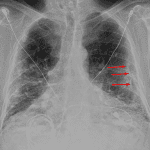

Age: 83

Sex: Male

Indication: Pre-op

Sample ReportBilateral pleural plaques and interstitial coarsening, most prominent at the lung bases. Findings are most suggestive of asbestosis. Consider chest CT for further evaluation.

No definite superimposed focal airspace disease.

Mild cardiomegaly.